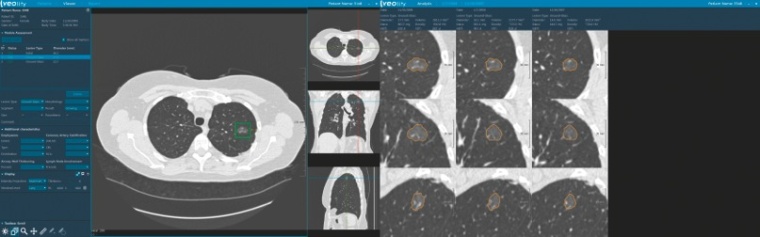

Mit Veolity bietet der Spezialist für Medizinsoftware MeVis Medical Solutions AG in Bremen/Deutschland eine dedizierte Befundstation für das CT-Lungenkrebs-Screening an. Basierend auf aktuellen Forschungsergebnissen optimiert Veolity den Arbeitsablauf und kombiniert die FDA-zugelassene automatische Lungenrundherderkennung (CAD - computer-aided detection) mit der automatischen Registrierung von Voraufnahmen und effizienter Befunderstellung. Die Befunde werden automatisiert nach aktuellen Standards und Richtlinien er-stellt - inklusive einem aktuellen Modell zur Vorhersage der Bösartigkeit. Automatische Messungen, Integration von Nebenbefunden, Bestimmung des Patientenmanagements und die Einbindung von Screeninglisten machen das System zu einer Komplettlösung für die Befundung von Lungenkrebs-Screening-CTs.

"CT-Lungenkrebs-Screening für Hochrisikogruppen wird jedes Jahr tausende Leben retten. Wir begrüßen die Entscheidung der CMS, nicht nur weil sie das Interesse an unseren Produkten fördert, sondern vor allem aufgrund des enormen Nutzens für die Patienten.", erklärt Bernd Kümmerlen, Produktmanager, MeVis Medical Solutions AG. "Mit Veolity versuchen wir die Arbeit für den Radiologen leichter zu machen, während wir gleichzeitig die Qualität verbessern und damit den Patientennutzen erhöhen. Lungenrundherde zu finden, zu vermessen und mit Voraufnahmen zu vergleichen, ist eine mühsame Arbeit. Veolity automatisiert viele dieser Schritte und ermöglicht Präzision in der Diagnostik durch die Rundherderkennung, durch objektive Messwerte und die Vergleichsfunktion zu Voraufnahmen."